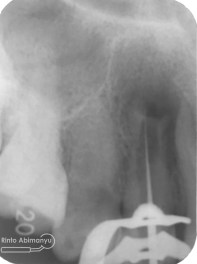

Pemeriksaan respon dingin pun menunjukkan hasil negatif, untuk menambah data dalam penegakan diagnosis maka dilakukan pengambilan ronsen pada gigi2 tersebut

Terlihat dari ronsen tersebut karies pada gigi 23 24 sudah mencapai pulpa… dari informasi pemeriksaan klinis dan ronsen maka didiagnosis gigi tersebut nekrosis.. Saya jelaskan kepada pasien mengenai kondisi gigi2 nya dan rencana perawatan yang akan saya lakukan…